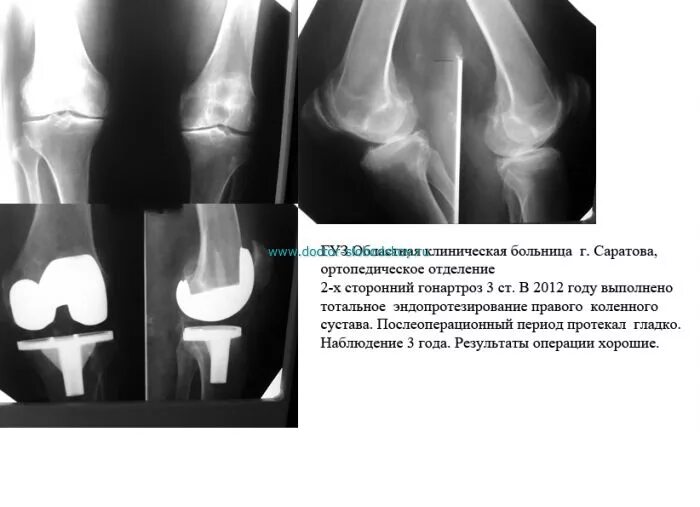

Форум после эндопротезирования коленного сустава